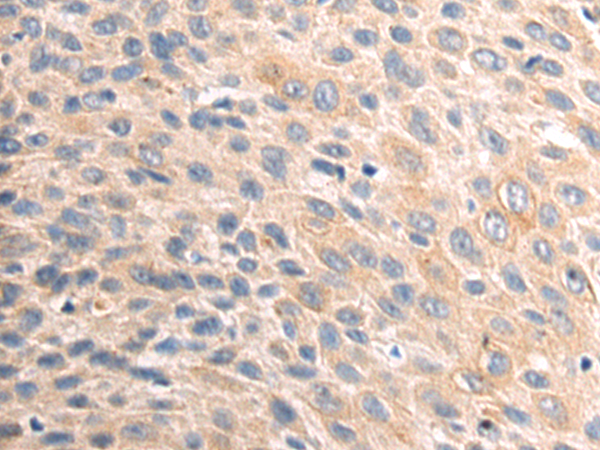

分类: 科研抗体货号: P08972别名: PHM27应用: IHC反应种属: Human, Rat